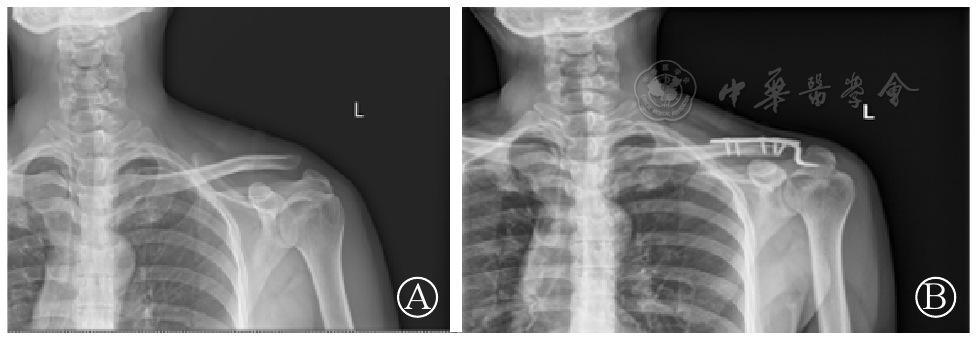

图3 带袢钛板组术前(图A)、术后(图B)X线片